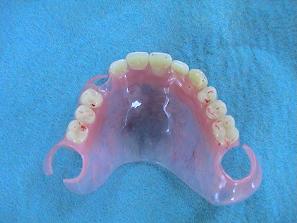

2. 作製したバネなし入れ歯

(バルプラスト)です